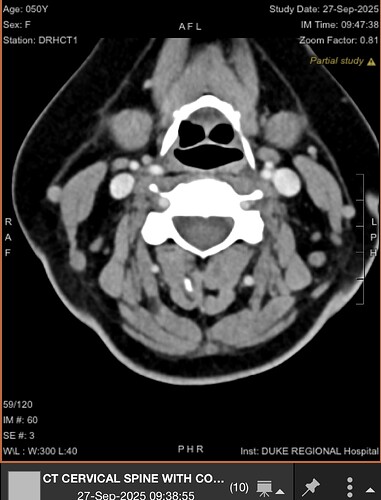

Ok...here's my CT...and no mention of styloids, but I think they are compressing IJV..Opinions?

brain fog, headache, ear fullness, conductive hearing loss, ear pain, dysphagia, gastroparesis, pulsatile tinnitus, tinnitus, balance problems, eye watering, double vision, ptosis of my eye, trouble with visual tracking, and exercise intolerance. I also have confirmed IIH. Of course, the radiologist did not comment on the CT Scans, so here I am asking for an opinion. I think I see jugular compression here between C1 and the styloid. I don’t have the CD, but I can get it.

@Nanc765 Good job posting helpful images! It sure looks like you have bilateral IJV compression. You have one very interestingly shaped styloid & on the other side it appears that you have a chunk of calcified stylohyoid ligament but not an elongated styloid, however, that image may have been taken further from the skull base than the other one so your styloid may be helping w/ the compression on both sides. Your symptoms do align with those seen w/ IJV compression.

I agree with the others. I think you’d benefit from bilateral styloidectomy above the level of C1 to open the IJVs up